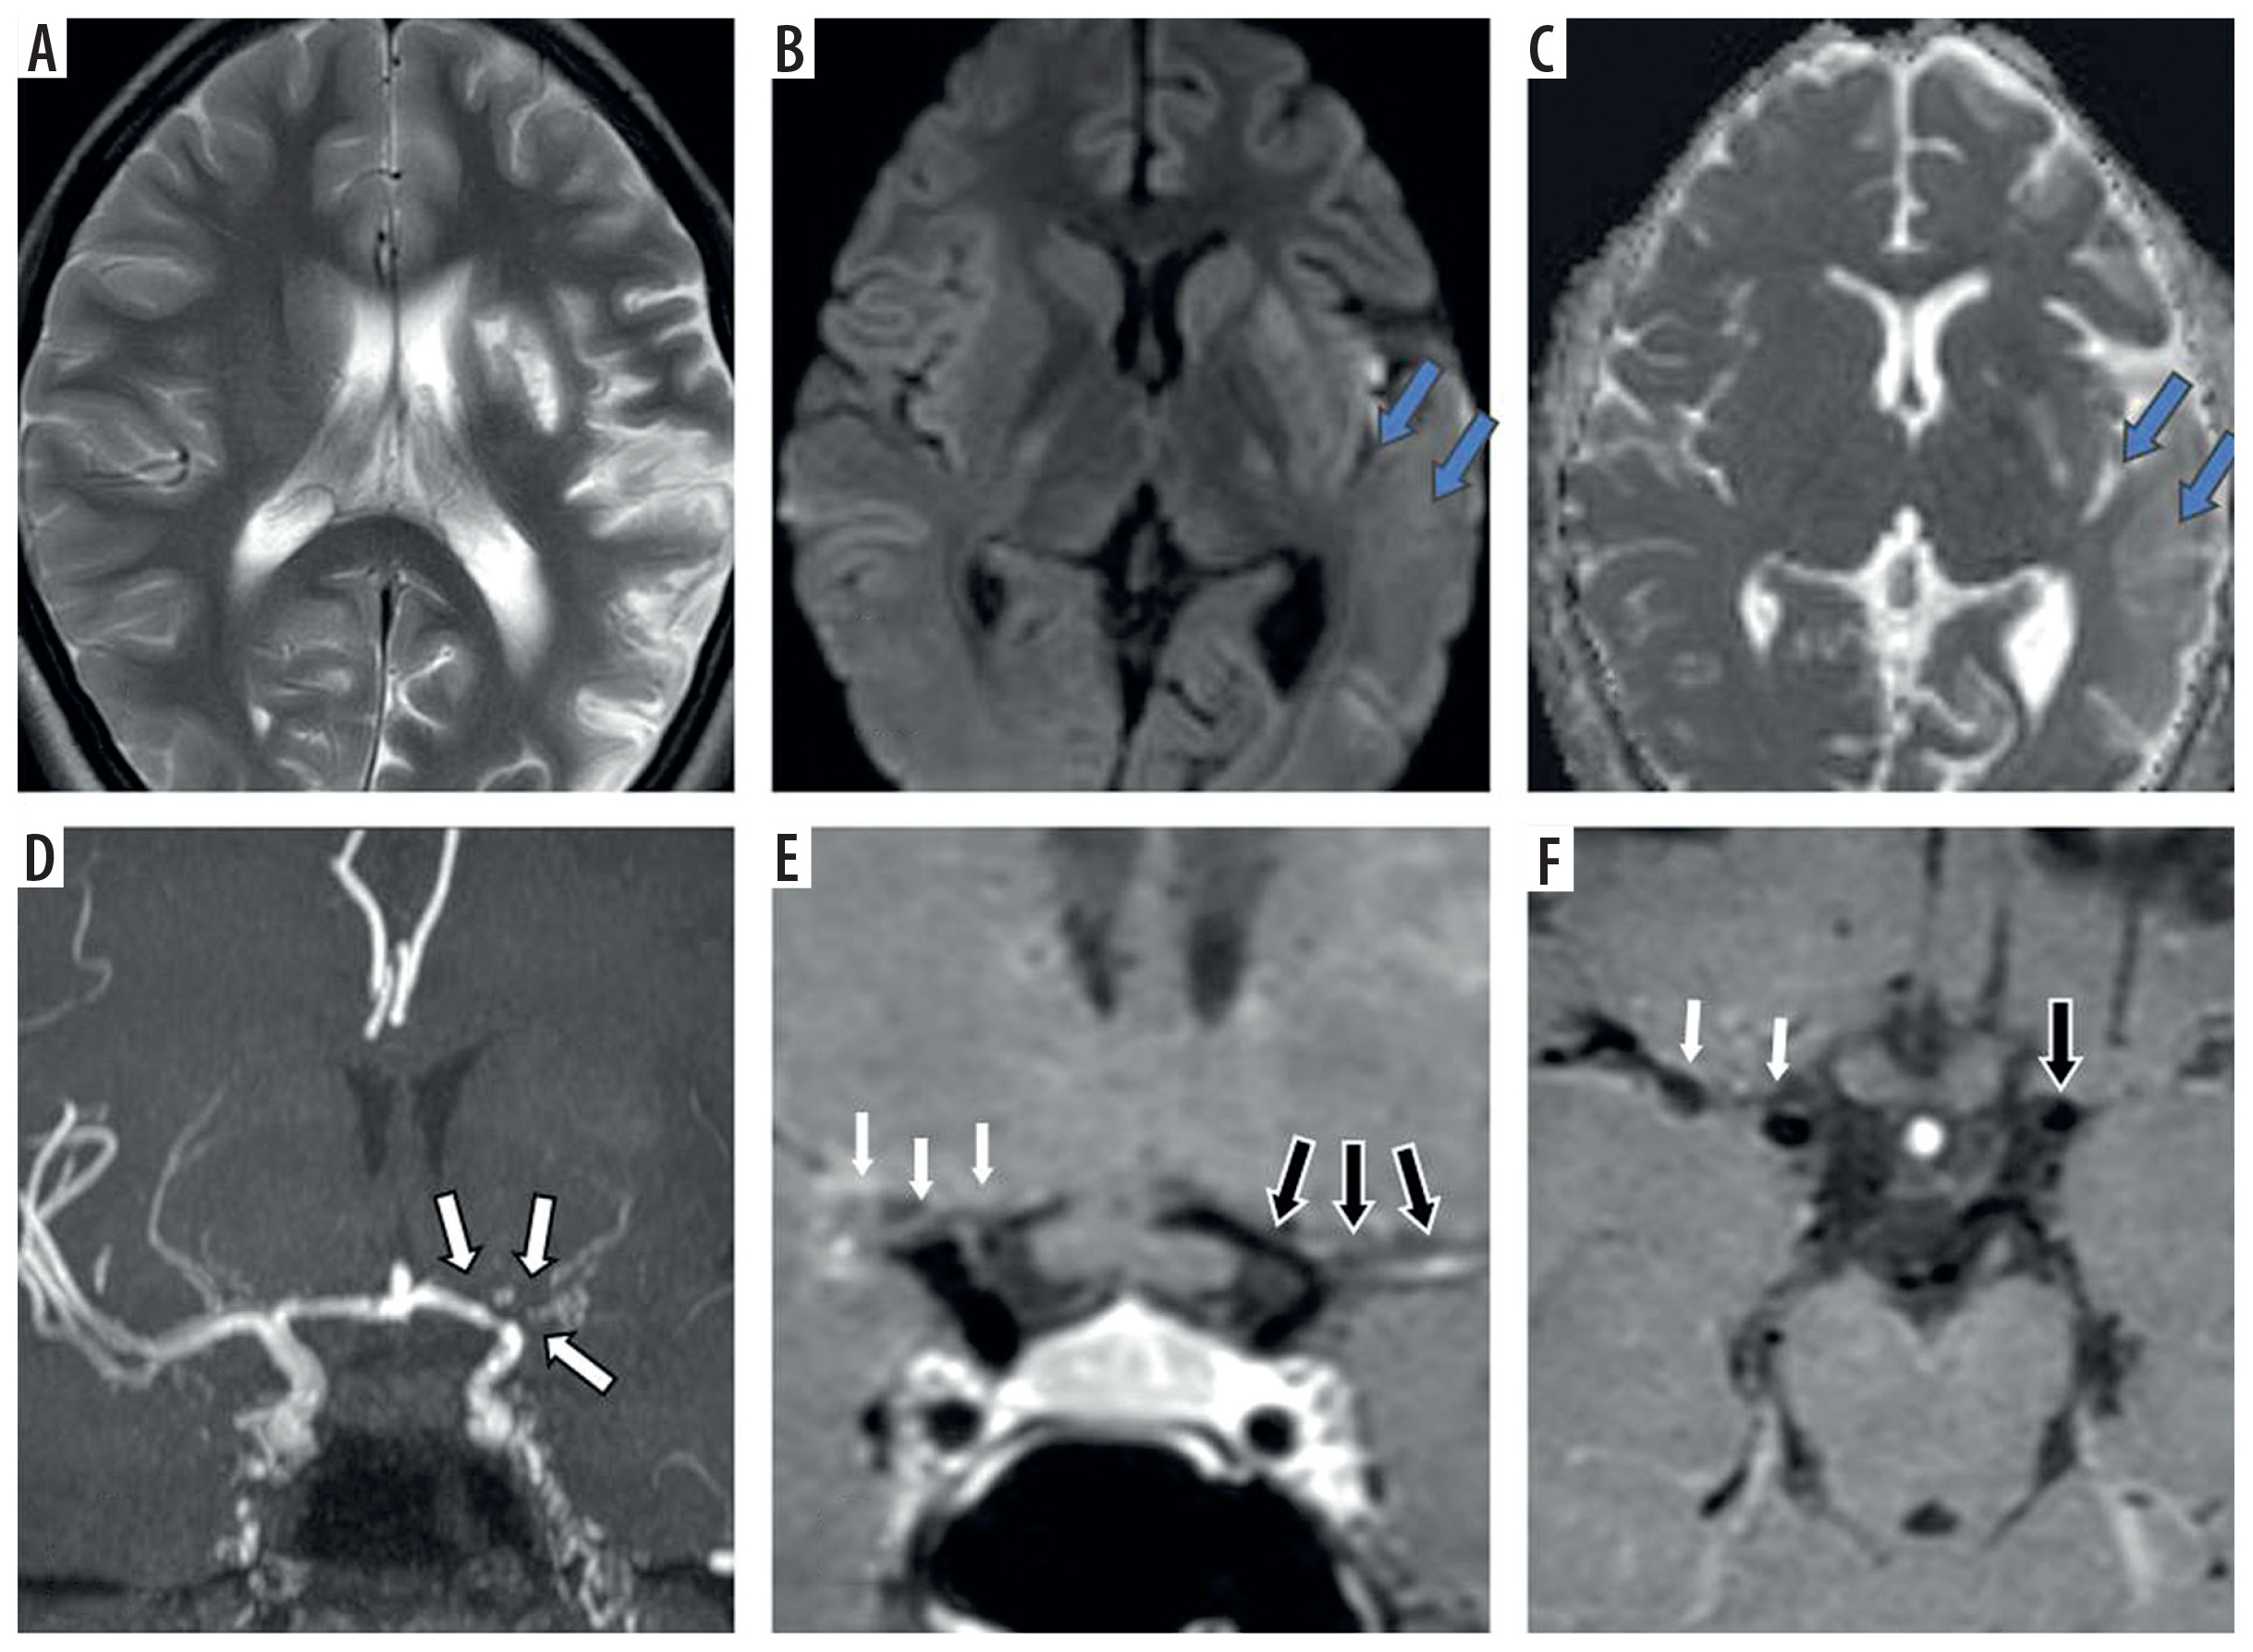

Figure 1

Fourty one-year-old female presenting with young stroke. Axial fluid-attenuated inversion recovery (FLAIR) (A), axial diffusion-weighted imaging (B) and axial view apparent diffusion coefficient map (C) image showing few foci of non-diffusion restricting FLAIR hyperintense signal intensity in right parieto-temporal lobe (white arrows in A and B). Coronal anterior maximum intensity projection time-of-flight magnetic resonance angiography (MRA) image (D) shows stenotic right supraclinoid internal carotid artery (ICA), right middle cerebral artery (MCA) with occluded right terminus ICA and right anterior cerebral artery (ACA) and also stenotic left terminus ICA (white arrows in D). Coronal pre-contrast vessel wall imaging (VWI) (E) and coronal post contrast VWI (F) showing vessel wall thickening (black arrows in E) and grade 2 concentric enhancement of right supraclinoid, terminus ICA, right MCA and ACA (black arrows in F). Grade 1 concentric enhancement also noted in left supraclinoid, terminus ICA and left ACA (white arrows in E and F)